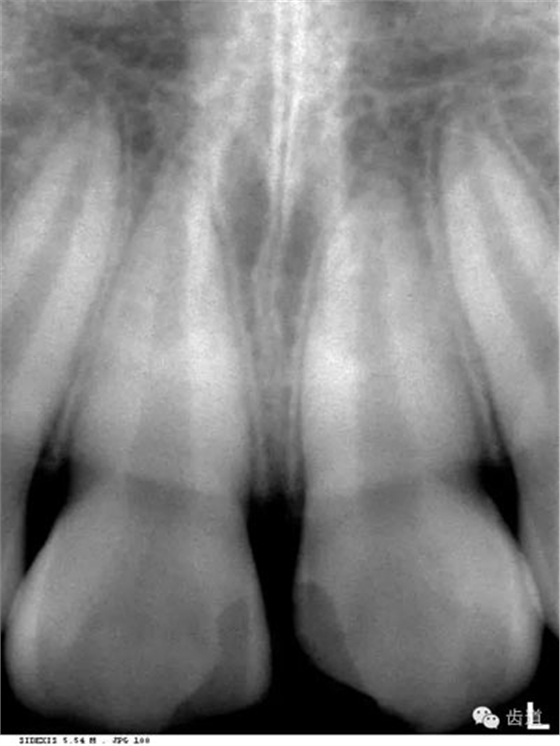

即固有牙槽骨,是牙槽骨的內(nèi)壁,圍繞牙根,骨質(zhì)致密而薄,X線片上顯示為包繞牙根的連續(xù)不斷的密度高的線條狀影像。

是介于牙槽窩和牙骨質(zhì)之間的結(jié)締組織。牙周膜的厚度一般在0.15~0.38mm之間。X線上顯示為包繞牙根連續(xù)不斷的密度低的線條狀影像,其寬度均勻一致